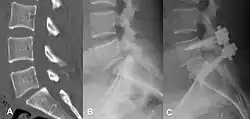

(A) CT sagittal view of a low grade slip.

(B) Lateral radiograph pre-operative intervention.

(C) Surgically treated with L5–S1 decompression, instrumented fusion and placement of an interbody graft between L5 and S1.